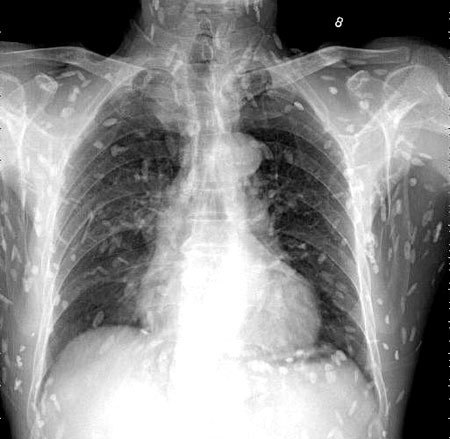

이 기생충들이 뇌조직으로 침투할 경우 생명에 위험을 초래할 수 있습니다. 회를 섭취한 남성의 사례에서도 복부통증과 피부가려움 등의 증상이 나타나, 엑스레이 결과 전신에 기생충이 퍼져 있는 것이 확인되었습니다. 따라서, 이러한 기생충에 감염될 경우 조기에 발견하고 치료하는 것이 매우 중요합니다.

마지막으로, 위에서 언급한 엑스레이 사진과 관련된 환자의 경우, 의료진은 해당 환자가 특별한 치료를 받지 않았다고 밝혔습니다. 만약 머리, 척수, 눈에 이상이 없다면 치료를 받을 필요가 없다고 말하고 있습니다. 또한, 사진 속의 유충들은 석회화되어 생존할 수 없는 상태이므로 특별한 조치가 필요하지 않다고 설명되었습니다. 그러나 해당 환자의 뇌에 낭종이 있는지 확인하기 위해 MRI 검사를 기다리고 있다고 전했습니다.